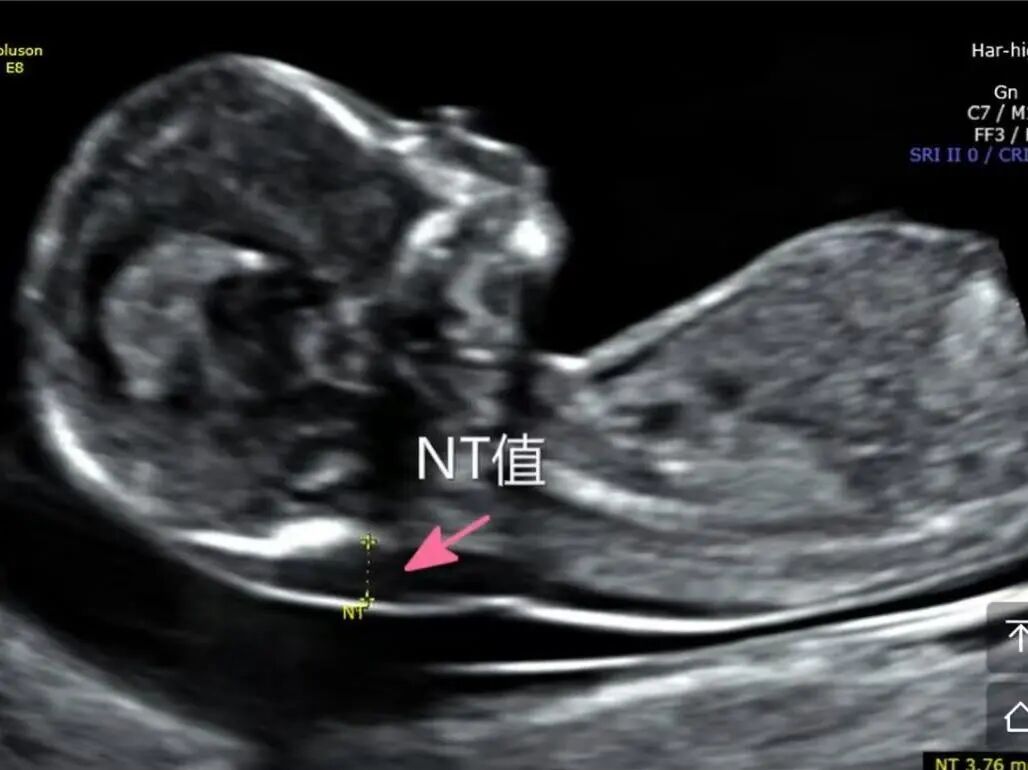

4月2日,贵州航天医院第55次晨读会由我院超声科医师敖春庆作学术交流,她以“中孕期产前超声筛查技术”为题,详细讲解了进修学习的成果,分享了科室实际开展的病例,阐述了未来的工作计划与展望,并结合典型病例图文分析等形式,强调了中孕期产前超声筛查的重要意义。 超声科专家简介 吴艳辉 中共党员,超声科学科带头人、主任,主任医师 临床擅长:从事超声诊断工作约30年,对心血管、小器官超声、超声引导下介入等具有丰富的临床经验。 骆科美 中共党员,超声科副主任医师 临床擅长:从事超声诊断工作33年,对胎儿心脏及颅脑、妇产超声、盆底超声等诊断具有丰富的临床经验。 胡大海 超声科副主任医师 临床擅长:从事超声工作17年,对心血管、外周血管、浅表器官超声诊断等具有丰富的临床经验。 刘 敏 超声科副主任医师 临床擅长:从事超声诊断工作20余年,对妇产科超声、心脏血管超声诊断具有丰富的临床经验。 敖春庆 超声科主治医师 临床擅长:对腹部、泌尿、妇科等超声诊断具有丰富的临床经验。 超声科简介 基本情况 贵州航天医院超声科配备多种超声检查设备(飞利浦彩超(IU-22、IU-Elite、HD11、Q5、Q7),迈瑞超声I9、DC-6、DC-8、GE-E8及床旁机,彩色超声诊断仪等),设有心血管诊室、妇产科诊室、腹部诊室、浅表小器官等检查室。 专科特色 四肢血管超声检查、双胎产前筛查及超声监护、超声造影检查技术、介入超声临床应用、经颅脑实质超声辅助筛查诊断帕金森病、女性性早熟超声诊断、盆底超声检查等。 NT超声检查 超声介入引导 肝脏超声造影 甲状腺造影 颅脑超声帕金森辅助检查 乳腺超声造影 上肢动静脉造瘘超声检查 双胎超声筛查 下肢血管超声检查 右心造影 诊疗范围 科室业务覆盖腹部、泌尿、妇科、产科(常规、NT筛查、III级筛查超声检查及高危妊娠监护)、成人心脏、外周血管、浅表器官(包含甲状腺、乳腺、阴囊、眼睛等)、颅脑(小儿颅脑、成人颅脑)、小儿肺超、造影、盆底、腹直肌、肌骨神经等检查及各种介入引导。 end